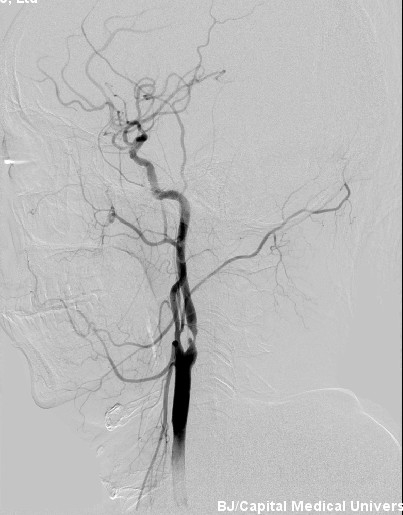

2012年9月19日,北京安贞医院脑卒中中心主任、中美脑中风协作组中方组长张勤奕教授于安贞医院为一例颈动脉重度狭窄患者实施了颈动脉内膜剥脱术,手术圆满成功。

患者王某某,男性,51岁,主因“发现左侧颈内动脉重度狭窄2年”入院。

患者3年前于安贞医院体检中心行颈部血管B超检查发现“左侧颈内动脉起始处轻-中度狭窄”,予以口服辛伐他丁、拜阿司匹林等药物治疗。5个前患者复查B超见“左颈内动脉重度狭窄”,为进一步诊治收住院。患者偶有发作性头晕,持续时间不定,既往高脂血症2年,无高血压、糖尿病、冠心病病史。

患者诊断明确,具备手术指征,无明显手术禁忌,2012年9月19日,张勤奕教授于安贞医院为其施行了颈动脉内膜剥脱术,手术圆满成功,患者恢复良好。